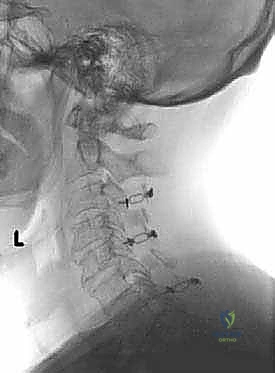

تُجرى عملية رأب الصفيحة العنقية تحت التخدير العام، وتستغرق عادةً ما بين ساعتين إلى أربع ساعات، اعتماداً على عدد المستويات الفقرية المتأثرة. يتبع الأستاذ الدكتور محمد هطيف بروتوكولاً جراحياً دقيقاً وصارماً لضمان أعلى نسب النجاح.

فيما يلي تفصيل لخطوات تقنية "الباب المفتوح" (الأكثر شيوعاً واستخداماً):

الخطوة 1: التحضير والتخدير ووضعية المريض

يتم إعطاء المريض تخديراً عاماً. يُوضع المريض على بطنه (وضعية الانبطاح - Prone Position) على طاولة عمليات خاصة. يتم تثبيت الرأس بعناية فائقة باستخدام جهاز تثبيت الجمجمة (Mayfield Tongs) لضمان عدم تحرك الرقبة ولو لمليمتر واحد أثناء الجراحة الدقيقة. يتم استخدام أجهزة مراقبة عصبية مستمرة (Neuromonitoring) لمراقبة وظائف الحبل الشوكي لحظة بلحظة طوال العملية.

الخطوة 2: الشق الجراحي والوصول للعظام

يُجري الدكتور هطيف شقاً جراحياً دقيقاً في منتصف الجزء الخلفي من الرقبة. يتم إبعاد عضلات الرقبة الخلفية برفق ولطف شديدين للوصول إلى الصفيحات العظمية (Laminae) للفقرات المستهدفة (غالباً من C3 إلى C6 أو C7).

الخطوة 3: إنشاء "المفصلة" (The Hinge)

باستخدام مثقاب جراحي دقيق (High-speed Burr) تحت التكبير الميكروسكوبي، يقوم الدكتور هطيف بنحت أخدود طولي على جانب واحد من الصفيحات العظمية (عند نقطة التقاء الصفيحة بالكتلة الجانبية). هذا